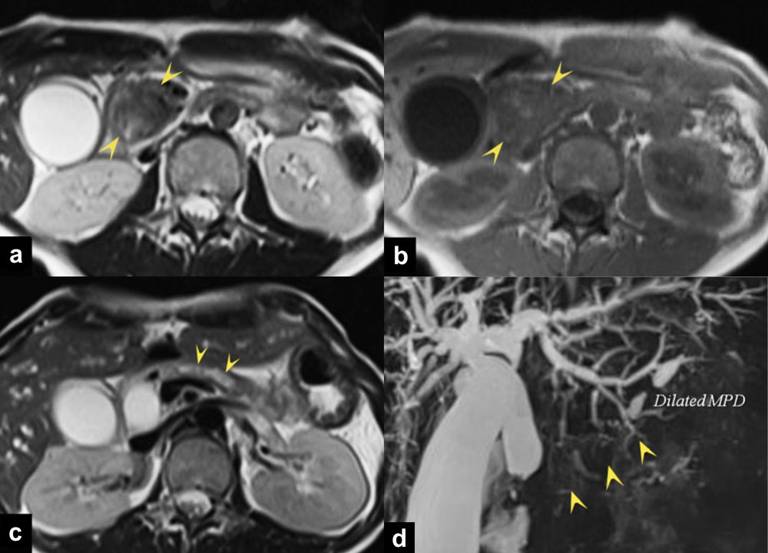

A 26-year-old woman was admitted to our hospital because of abdominal pain. Laboratory examination showed the elevated serum levels of bilirubin and hepatic enzymes. Her medical history was not remarkable. Laboratory findings showed abnormal liver function (AST: 118 IU/L, ALT: 91 IU/L) and obstructive jaundice (total bilirubin: 11.53 mg/dL). The carbohydreate antigen (CA) 19-9 (106 U/mL) was moderately elevated but the carcinoembryonic antigen (CEA) showed normal range. Triple-phase enhanced computed tomography (CT) demonstrated a well-enhanced mass on the arterial dominant phase in the head of the pancreas (Figure 1ac). The mass grew within the lumen of the MPD in the body of the pancreas, with dilatation of the upstream MPD (Figure 1bd). There was a difference of the contrast-enhancement pattern between the main tumor of the pancreatic head and the intraductal lesion of the pancreatic body: an early contrast-enhancement with its persistence till the delayed phase in the head lesion, and an early contrast-enhancement with its decrease during the delayed phase in the intraductal tumor of the body. Dilation of the bile ducts was seen probably due to the tumor compression, and direct tumor invasion to the duodenum was suspected. Lymph node enlargement at the portocaval space was identified, but there was no metastatic lesion in the major organs. On magnetic resonance (MR) imaging, the pancreatic head lesion was observed as non homogeneously low signal intensity (SI) on T2-weighted imaging (WI) (Figure 2a) and low SI on T1-WI (Figure 2b). The intraductal lesion of the pancreatic body showed high SI on T2-WI (Figure 2c). MR cholangiopancreatography showed obstruction of the MPD in the pancreatic head to body, with dilatation of the upstream MPD (Figure 2d).

Figure 2. The pancreatic head mass is seen as inhomogeneously low signal intensity (arrowheads) on T2-weighted (a.) and T1-weighted (b.) images. The intraductal lesion of the pancreatic body showed high signal intensity (arrowheads) on T2-weighted image (c.). MR cholangiopancreatography (d.) shows obstruction of the main pancreatic duct in the pancreatic head to body (arrowheads), with dilatation of the upstream duct. |